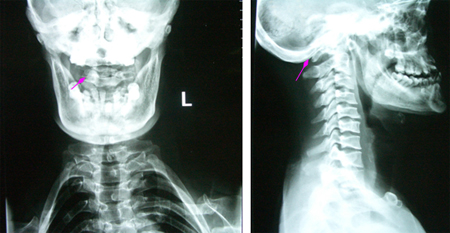

男性,35岁,自幼颅颈、双肩发育异常,双手、上肢肌萎缩3年,加重1月,伴走路不稳。查体:短颈、发髻低、双肩狭小畸形、脊柱侧弯,双上肢及躯干片状感觉障碍,双上肢肌力3-4级,远端更差伴双手爪形,双侧手指伸直困难,双侧病理征阳性。术前影像学资料显示:颅底凹陷、寰枕融合、颈椎生理曲度消失伴退行性改变,小脑扁桃体下疝入椎管伴脊髓空洞(达T8水平)。